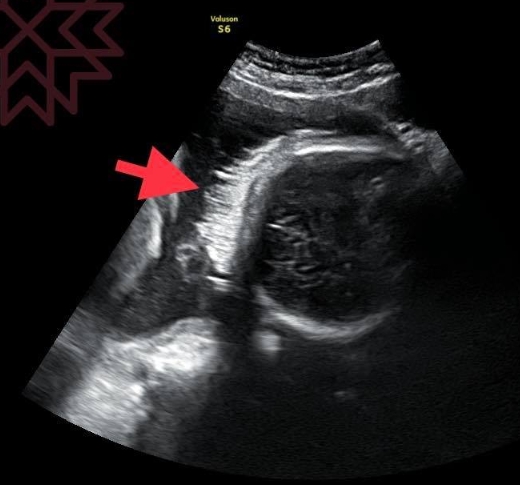

▼醫師蘇怡寧,上傳胎兒的超音波照,說明寶寶在孕婦肚子裡能長頭髮。(圖/翻攝自蘇怡寧醫師愛碎念)

婦產科醫師蘇怡寧昨(23日)日在臉書PO文表示,曾遇到不少媽媽詢問「胎兒有頭髮嗎?」為了更清楚回應民眾的提問,他直接貼出一張寶寶的超音波照,並簡單解說「頭髮就在超音波照片箭頭所指的地方,如果用動態檔還會看到正在飄的頭髮」!

蘇怡寧還補充說明,其實寶寶髮量的多寡取決於「遺傳」,雖然有些胎兒早在媽媽的肚子裡就有濃密的頭髮,有些胎兒的髮量卻很稀疏,或幾乎沒有頭髮,但這並不影響寶寶日後長大的真實髮量。還記得,自己的兒子在剛出生時也是個光頭,但如今兒子已長成頭髮茂密的10歲小孩,希望父母們不要過度擔心。